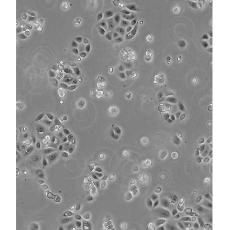

SW 1990

中文名稱 人胰腺癌細胞

生長特性 adhere

形態特征 epithelial

細胞描述 1978年從胰腺外分泌腺的胰腺腺癌II期患者的脾轉移灶中建立了SW 1990細胞株。 報道該細胞的植板率為29%。